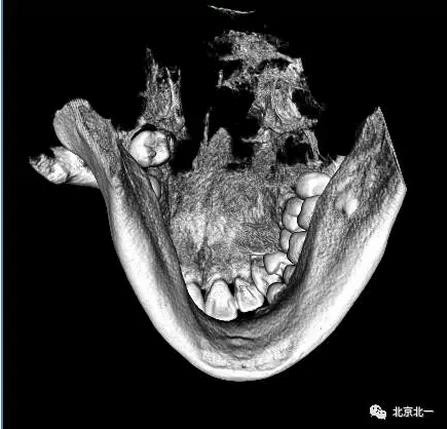

圖四:三維重建

圖五:三維重建可見牙冠突破舌側

圖九:重建后可見牙冠位于第二磨牙遠中,舌側傾斜。